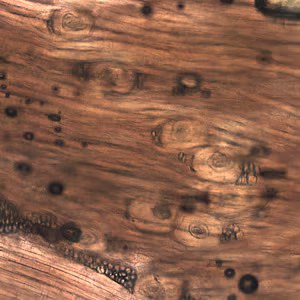

A huntsman killed a bear and prepared it for eating and freezing by cutting it into roasts, steaks, and grinding the trimmings. Later that same day, he ate a burger made from some of the fresh meat and cooked rare. Approximately two and a half to three weeks later, the hunter experienced fever, diarrhea, and muscle pain.